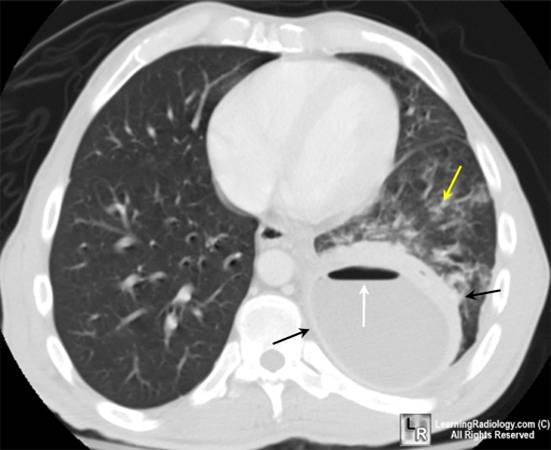

weekly clinical round for undergraduate from 8 to 11 AM during which interpretation of CHEST X rays was done for all cases of cardiothoracic surgery, gived by 2 staf member for 3 months